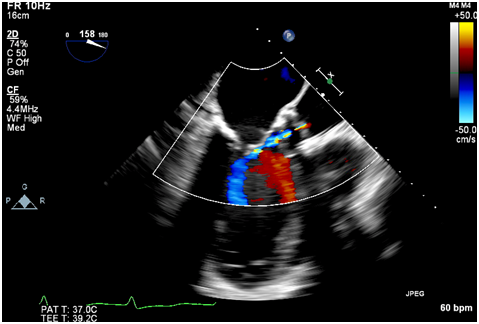

Figure 2 Intraoperative TEE post deployment showing mild central aortic insufficiency.

Immediately after the prosthetic valve deployment, intraprocedural TEE revealed a 20 x 9.5 mm mobile echo density attached to the ventricular side of the strut along the right coronary cusp. The structure intermittently prolapsed through the leaflets of the newly placed valve prosthesis during systole (Figure 1A, 1B). However, only mild (1+) central aortic regurgitation was noted (Figure 2). There was no left ventricular outflow tract obstruction and the prosthetic valve leaflet excursion was otherwise normal. The peak and mean aortic valve gradients were 7 and 4 mm Hg respectively post deployment.